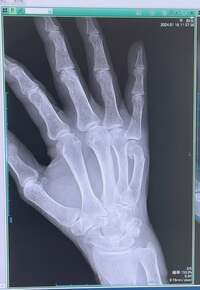

この日は「結論からご報告します」と述べ「ワイヤー手術はせずに済みました」と報告。「先生のもう一度折って正しい位置にはめるこの判断と処置が素晴らしかったのですね」とコメントし「一目瞭然ですよね 比較すると良く分かります」と処置前と後のレントゲン写真を公開。医師からも「良いですね!」と言われたことを明かした。